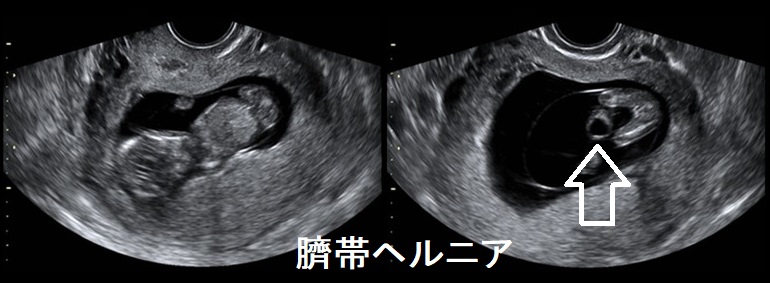

臍帯ヘルニアは、臍帯が付いていた所から腸管・胃・肝臓などが腹腔外へ脱出した状態です。

臍帯ヘルニアは必ずしもメルカゾールが原因とは限りません。

臍帯ヘルニアは染色体異常でも起こります。染色体異常によるものは、停留精巣などの泌尿生殖器奇形、中枢神経系の重症奇形、上気道狭窄・閉鎖、多指症など多発奇形を合併します。

臍帯ヘルニア 超音波(エコー)画像[Am J Case Rep. 2020 Sep 8;21:e926310.]